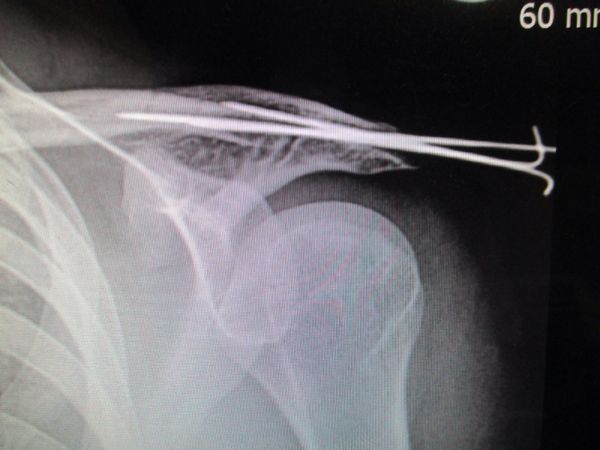

しかも、初回脱臼の年齢が低ければ低いほど、再脱臼する確率は高く、10代では68%、代で52%、30代で25%、40代以上で17%と報告されています(Itoi E, JBJS A, 07より引用)。 肩関節脱臼の治療は? 治療は基本的に脱臼整復して肩を固定する保存治療です。このページでは 肩鎖関節脱臼(けんさかんせつだっきゅう) という 鎖骨の先端がもとの位置から外れてしまう状態 に対する治療方法について解説いたします。 肩鎖関節脱臼というケガは、重症度にもよりますが、治療法もまだ定まっておらず、医師によっても意見が分かれることがよくあります。 命に関わるケガではありませんので、治療法の最終決定は患者 肩関節は非常に可動性の高い構造となっているため、脱臼が起こりやすい関節です。 若年者の脱臼は反復性肩関節脱臼(繰り返し起こる脱臼)の原因となりやすいです。 《誘因・原因》 一般に肩甲骨と上腕骨の間の関節での脱臼を意味します。

治療 初回脱臼の整復後は断裂した関節包などの軟部組織が修復するまで、約36週間の固定が必要です。 上肢の固定肢位については諸説ありますが、従来からある固定方法では若年者の場合90%は再脱臼を来たし、反復性脱臼へ移行するといった報告もあり、十分な治療成績は得られてません。 近年では、肩関節を 外旋位に保って固定する方法 が損傷組織の修復には